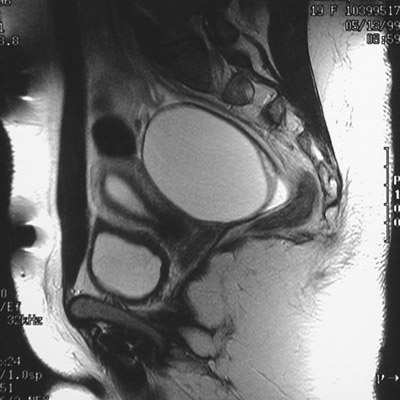

This MRI scan of the pelvis in sagittal view demonstrates a

large discrete fluid-filled mass

consistent with a cystadenoma of the ovary. The

uterus

bladder

sacrum

are visualized as well.